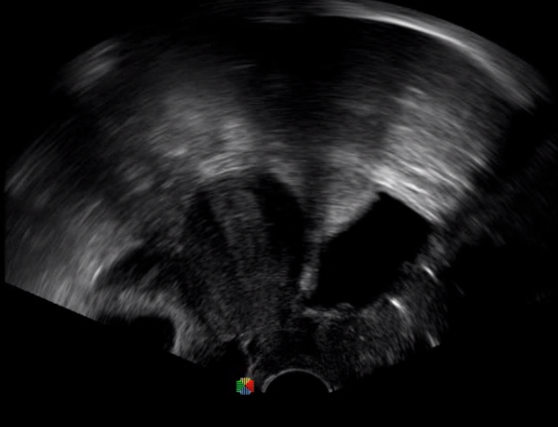

腹腔鏡超聲是超聲技術和腹腔鏡技術的融合,腹腔鏡超聲降低了對超聲探測深度的要求。由微小切口進入手術部位,多角度彎曲可選擇,降低手術難度及風險;與受檢組織器官直接接觸,有效避免氣體干擾。

應用科室:麻醉科、手術室、普外科、泌尿外科、婦產科、腫瘤科、介入科等

腹腔鏡下 肝臟占位